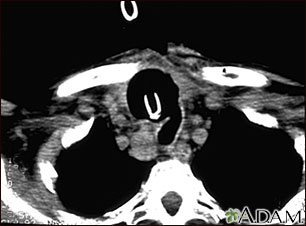

Tomografía computarizada de cáncer de tiroides

TC de la parte superior del tórax que muestra un tumor maligno (cáncer) tiroideo. Se ha producido la destrucción y muerte (necrosis) del tejido normal en el área oscura alrededor de la tráquea (marcada por la punta blanca en forma de U del tubo respiratorio), como resultado del crecimiento del tumor.